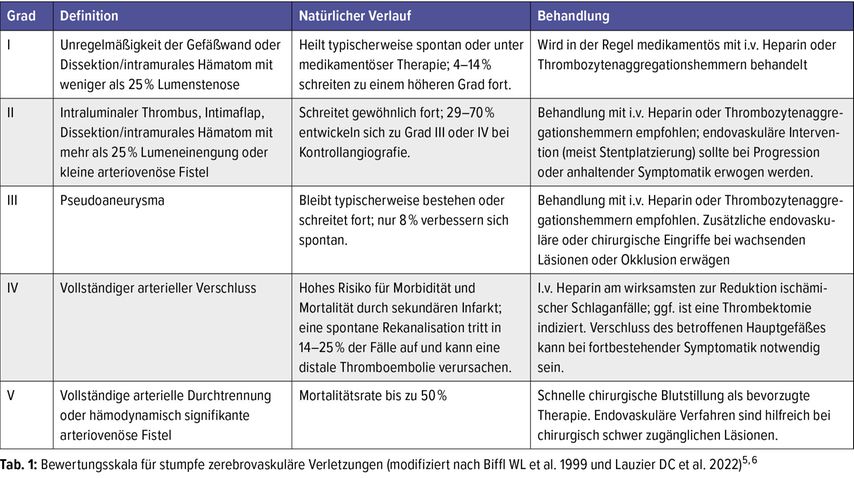

Zur Klassifikation von stumpfen zerebrovaskulären Verletzungen der HWS (Blunt Cerebrovascular Injury; BCVI) hat sich die Graduierungsskala nach Biffl et al.8 durchgesetzt. Hier wurden die Gefäßläsionen anhand der CTA oder DSA klassifiziert und das therapeutische Vorgehen von einer Arbeitsgruppe nach Lauzier DC et al.9 2022 abgeleitet (Tab.1).10

Tab. 1: Bewertungsskala für stumpfe zerebrovaskuläre Verletzungen (modifiziert nach Biffl WL et al. 1999 und Lauzier DC et al. 2022)5,6